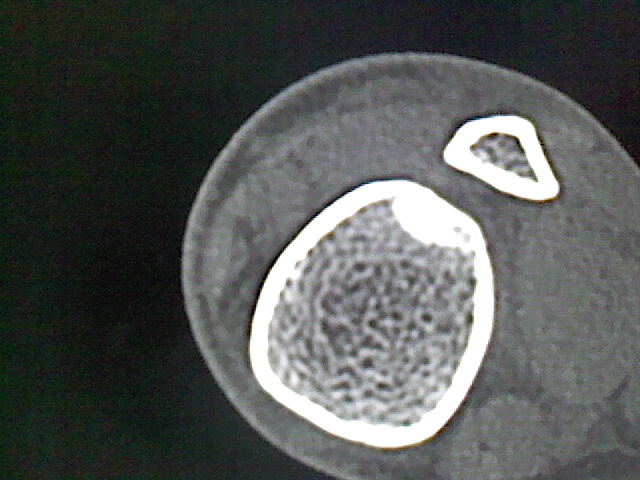

男,33岁,外伤后拍片发现,左侧胫骨可见一高密度影

考虑,右胫骨下端内生性骨瘤。

考虑右胫骨下端内生性骨瘤。

内生软骨瘤可能

骨样骨瘤。

可见瘤巢,考虑骨样骨瘤

内生骨瘤可能性大,不知病人有何症状,不除外骨样骨瘤

良性骨肿瘤,以内生软骨瘤或骨纤维瘤可能大。请上传骨窗。